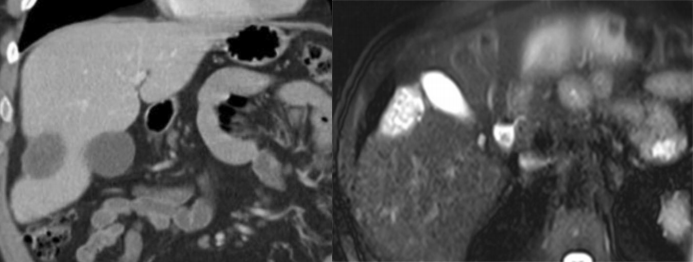

肝融合性纤维化,肝局部体积缩小,肝包膜凹陷,病灶呈 T2-FS 中等高信号,信号均匀,增强后动脉期强化不明显,延迟期呈均匀强化,相对肝实质呈高信号,内见正常走形血管影。